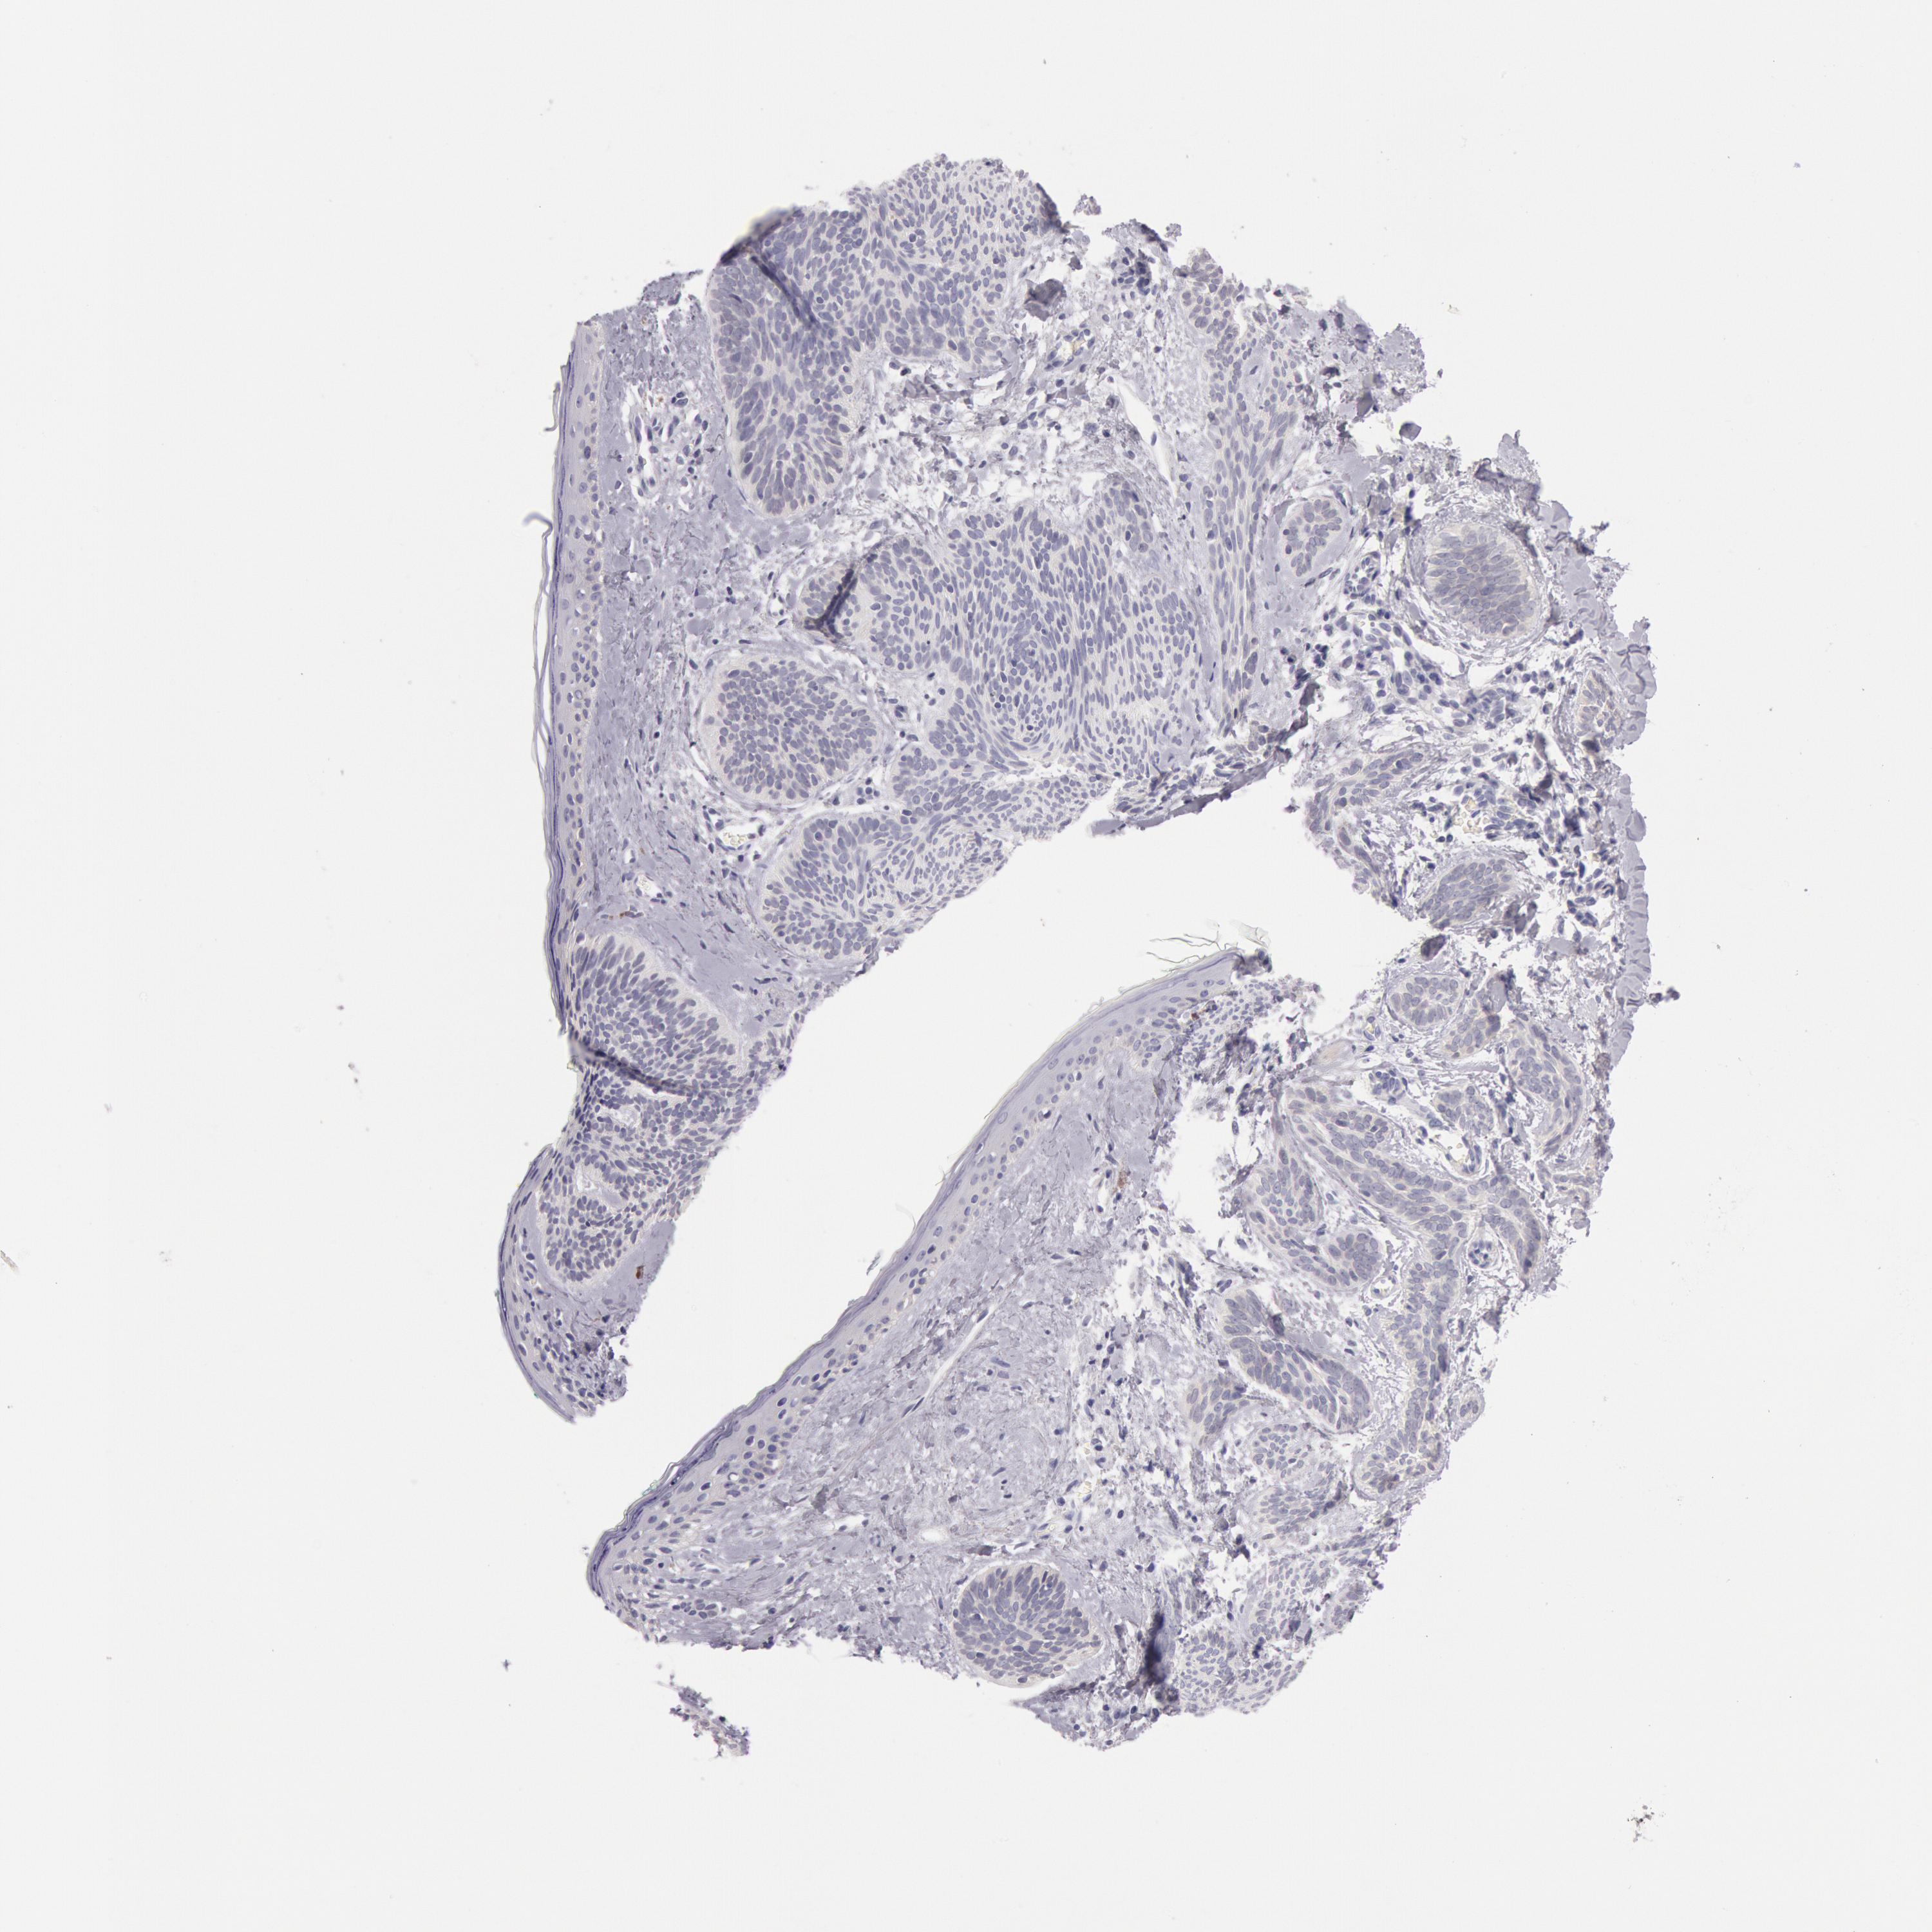

SKIN CANCER - Protein expressioni

A mouse-over function shows sample information and annotation data. Click on an image to view it in a full screen mode. Samples can be filtered based on level of antibody staining by selecting one or several of the following categories: high, medium, low and not detected. The assay and annotation is described here.

Each image is clickable and will lead to virtual microscopy that enables deeper exploration of all samples and also displays staining intensity scores, fraction scores and subcellular localization as well as patient and tissue information for each sample.

HPA001200

Staining

High

Medium

Low

Not detected

Squamous cell carcinoma, NOS

Basal cell carcinoma

Squamous cell carcinoma in situ, NOS

Squamous cell carcinoma, metastatic, NOS